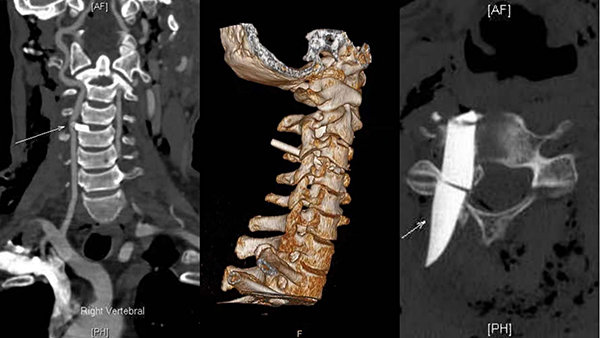

急診外科主任姚愛明主任醫(yī)師接到病情匯報后很快抵達現(xiàn)場,CT結(jié)果令現(xiàn)場所有人大吃一驚:CT顯示玻璃碎片像尖刀一樣刺入頸椎3/4之間,卡在脊髓和椎動脈之間。此處脊髓位置較高,一旦損傷輕則癱瘓,重則隨時心跳呼吸驟停而亡,彌漫性氣顱提示硬膜已經(jīng)破裂!CTA顯示椎動脈被明顯壓迫,隨時可能破裂出血,導(dǎo)致失血性休克、大面積缺血性腦梗死,腦疝甚至死亡!且殘留玻璃碎片中間斷裂破碎,可能無法完全取出,給手術(shù)增加了極大的難度!

術(shù)中發(fā)現(xiàn),玻璃碎片從舌骨及甲狀軟骨之間,由左前至右后刺穿喉咽前后壁,并繼續(xù)向后刺穿并卡入頸3/4椎體之間,硬膜破裂腦脊液外漏,椎動脈未見明顯破裂出血。經(jīng)過4個多小時緊張有序的手術(shù),姚愛明主任帶領(lǐng)其團隊成功取出殘留體內(nèi)的碎片,并行硬膜修補。劉穩(wěn)主任進行了喉咽部損傷的探查及修補。兩次術(shù)中喚醒及術(shù)后觀察患者四肢活動良好,手術(shù)成功!術(shù)后護送至神經(jīng)外科ICU監(jiān)護治療,患者后續(xù)仍需渡過氣管瘺、傷口感染、肺部感染、腦脊液漏及顱內(nèi)感染等難關(guān)。